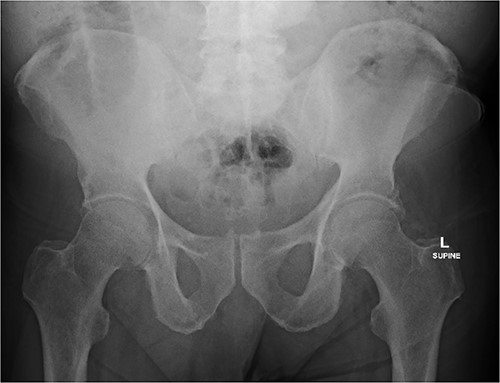

During the push enteroscopy the hearing aid could not be found despite thorough inspection of duodenal diverticula. The procedure was assisted by image intensifier guidance, and upon consultation with the onsite radiologist, the impression was that the hearing aid was in a jejunal diverticulum rather than a duodenal diverticulum. The procedure was abandoned and a single balloon assisted enteroscopy was planned for the following day. Prior to the procedure, the foreign body could not be located on the initial scout x-ray, and it was presumed to have passed naturally. Follow up formal x-rays again did not identify a foreign body (Figs 4 and 5), and the patient has been well since.